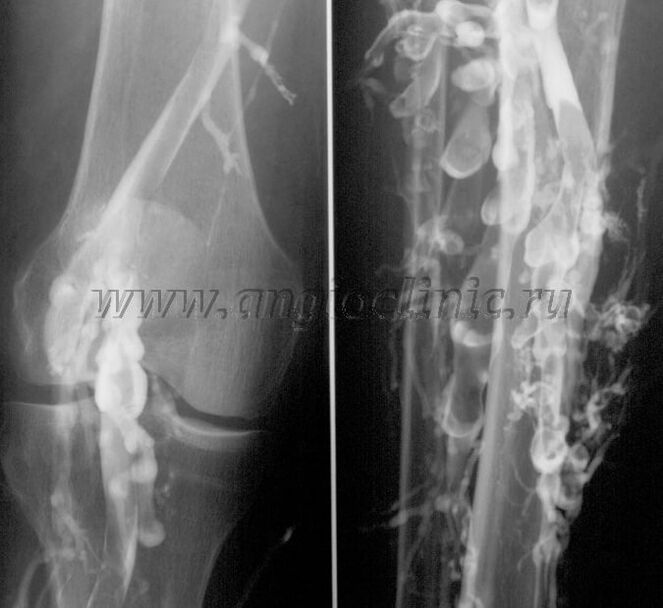

造影静脈造影

通常、静脈病理の完全な診断には超音波スキャンで十分ですが、場合によっては、特に静脈瘤の再発や続発性静脈瘤の場合、深部静脈系と表在静脈系の状態の関係を研究する必要があります。

これらの問題を解決するために造影X線検査が使用されます。伏在静脈を穿刺し、造影剤を投与します。コントラストの動きは X 線装置のモニターで観察され、必要なすべての検査と投影が実行されます。現在、静脈瘤に対する静脈造影検査が使用されることは非常にまれです。